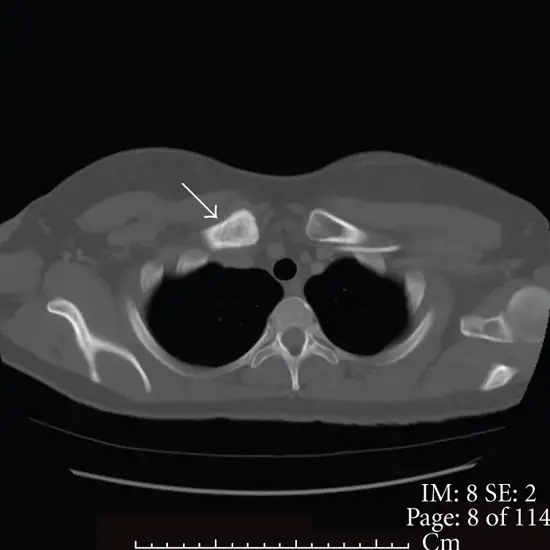

CT Scan Left Clavicle is an imaging procedure used to visualize the left clavicle. The clavicle is the region located between the ribcage and shoulder bone. This scan helps detect the existence of inflammation, infection, swelling, or bruising in the left clavicle and its surrounding soft tissues. It helps the doctor in diagnosing conditions such as osteoarthritis, rheumatoid arthritis, and fractures.

• To detect/diagnose fractures of the bones of the left clavicle that are not visible on a simple X-ray

• To detect the presence of infection, injury, inflammation, or swelling in the left clavicle and its surrounding soft tissues like the muscle and tendons